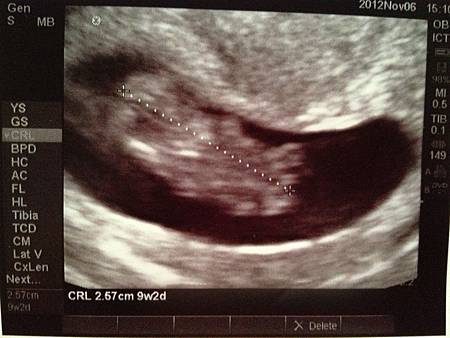

11/6 約了蔡醫生再次檢查

原本這次產檢應該是會在台灣作的~ 不過由於回台灣的前兩天有流一點咖啡色的分泌物

所以臨時決定取消機票還有去首爾的行程 為了寶寶可以平平安安的我還是暫時待在這裡好囉